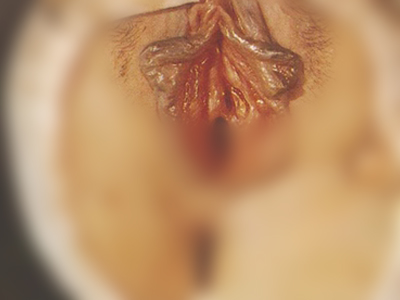

一期梅毒症状图片

硬下疳好发于外生殖器,典型的硬下疳初起为小红斑,迅速发展为无痛性炎性丘疹,数天内丘疹扩大形成硬结,表面发生坏死形成单个直径为1-2cm圆形或椭圆形无痛性溃疡,境界清楚,触之具有软骨样硬度,表面有浆液性分泌物,传染性极强。